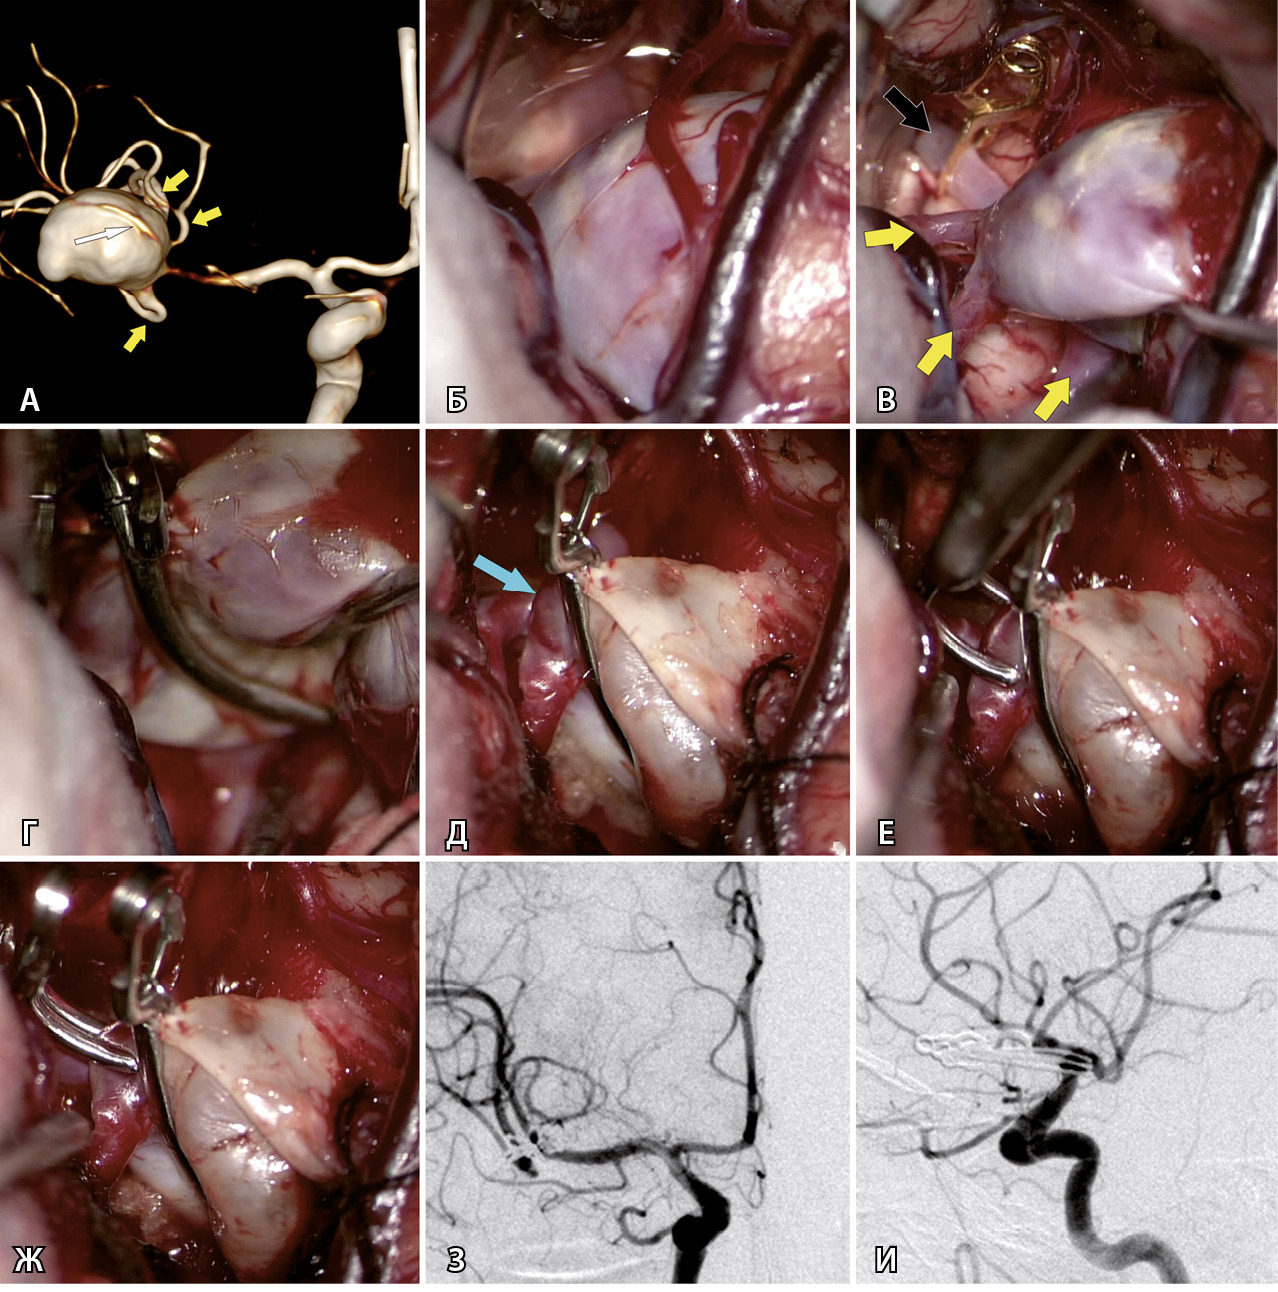

Рис. 1. Клипирование гигантской аневризмы средней мозговой артерии (СМА) справа у пациентки Г., 59 л. А – при компьютерной томографической ангиографии определяется гигантская аневризма трифуркации СМА справа (желтыми стрелками указаны три М2-ветви СМА справа, белой стрелкой указана припаянная к телу аневризмы передняя височная артерия). Б – интраоперационное фото: отмечается выступающее в сильвиеву щель тело аневризмы СМА справа. В – после наложения временной клипсы на М1-сегмент справа (указан черной стрелкой) мешок аневризмы релаксировал, что позволило выделить и визуализировать три М2-ветви (указаны желтыми стрелками). Г – длинная изогнутая клипса наложена на шейку аневризмы. Д – после клипирования наблюдается небольшой остаточный участок шейки аневризмы (указан стрелкой) у теменного М2-сегмента. Е – наложение на остаточный участок шейки аневризмы маленькой изогнутой клипсы. Ж – результат клипирования шейки аневризмы двумя клипсами. З – контрольная церебральная ангиография в прямой проекции. И – контрольная церебральная ангиография в боковой проекции